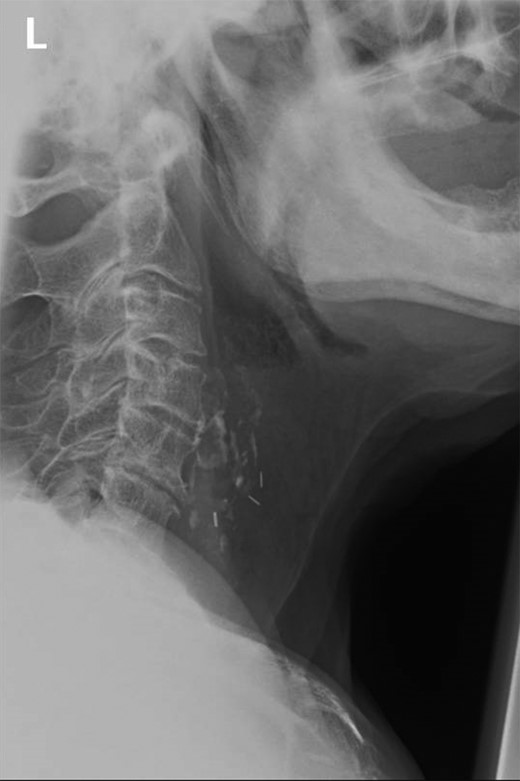

Lateral view soft tissue neck radiograph demonstrating calcified lesion at level of C4–C5. Presence of previous ligation clips noted from previous laryngectomy.

Authors present an 80-year-old male attending with symptoms of dysphagia, drooling and globus sensation. Symptoms commenced during the patients evening meal. The patient reported eating pork, with no recollection for presence of bones. The patient’s medical history was complicated by previous squamous cell carcinoma of the vocal cords requiring laryngectomy plus neck dissection 8 years previously. Despite multiple attempts to swallow the food bolus, supplemented by assistance from carbonated drinks, no improvement was observed. Doctors performed naso-endoscopic evaluation of the pharynx, and no visualization of the food bolus was noted. For completeness, a lateral soft tissue neck x-ray was performed. Radiographs demonstrated the presence of a calcified area within the larynx thought, initially by junior colleagues, to represent a foreign body (Fig. 1). The patient was placed upon regular hyoscine butylbromide injections, and observed until morning with a plan for rigid endoscopic evaluation plus removal of calcified piece of meat.